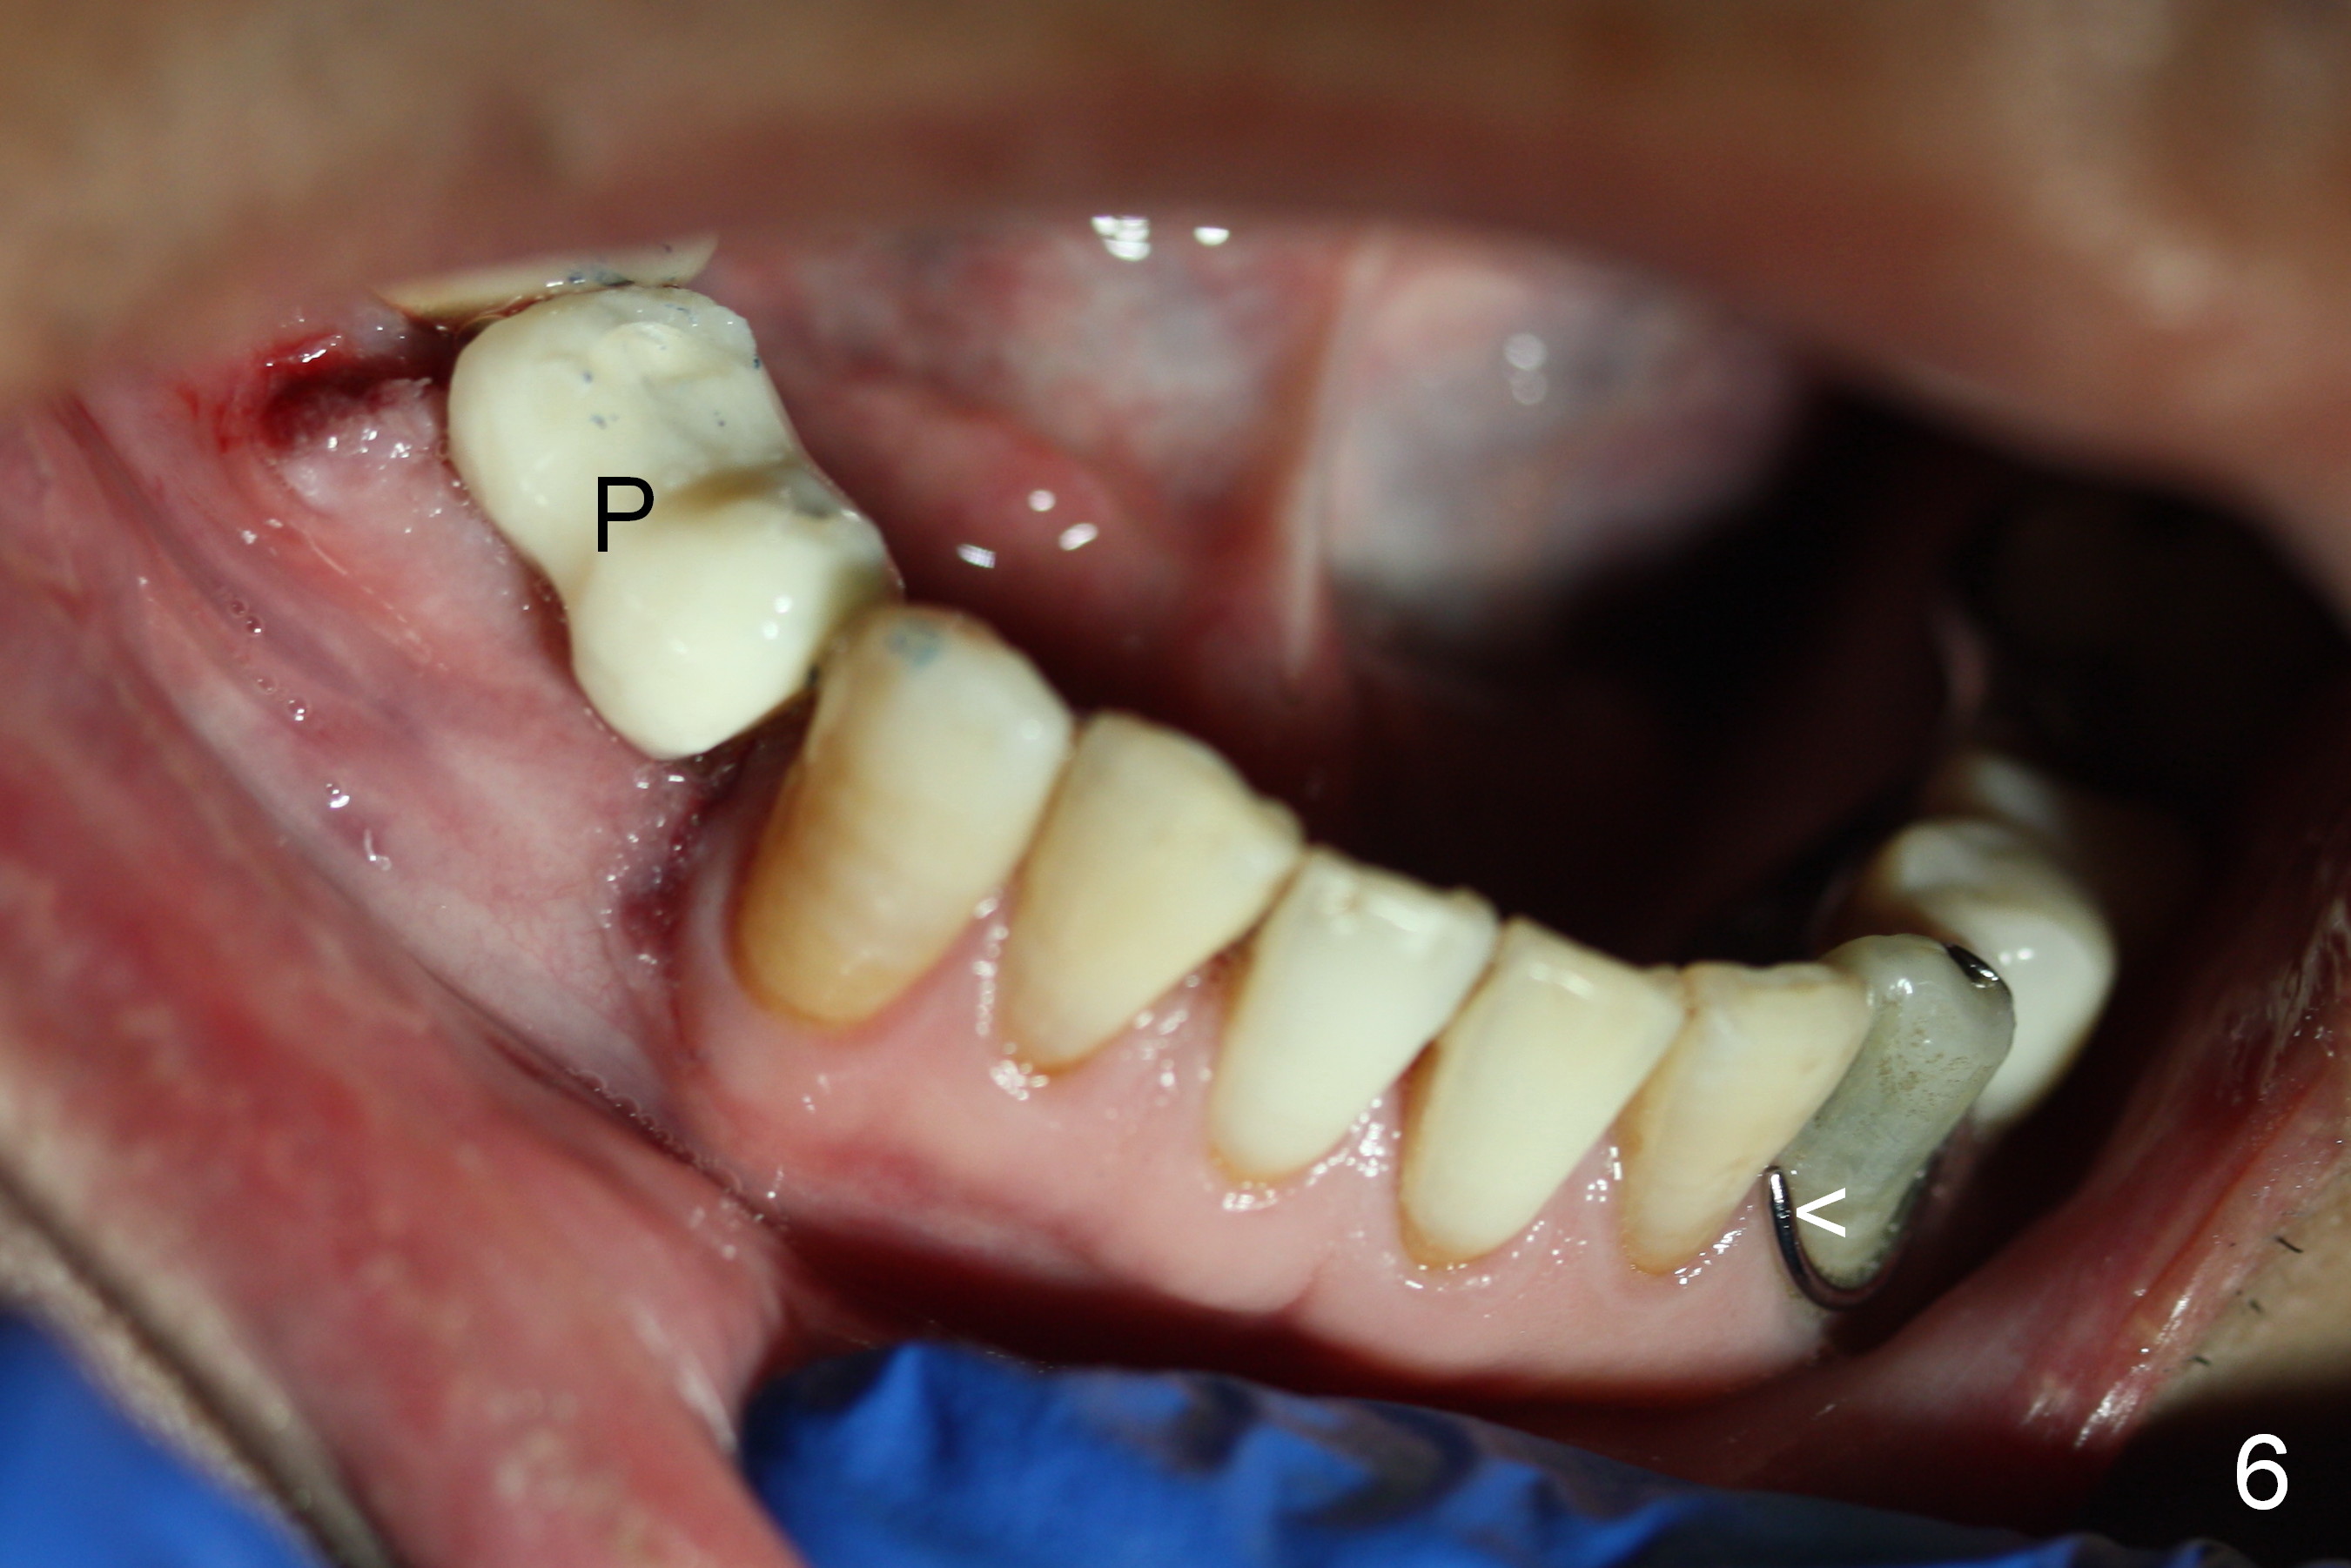

The patient has lost several teeth, which are replaced by removable partial dentures. He wants to have implants in the lower right first because of loss of a buccal clasp over the tooth #30 (Fig.1). When the lower partial is removed, a narrow soft tissue band is visible in the edentulous area. The hard tissue ridge is approximately 3 and 5 mm buccolingually at the sites of #28 and 29, respectively (Fig.3 after initial osteotomy). To place 2 adjoining implants at the same level, the treatment plan is modified: a 3 mm 1-piece implant will be placed at #28, while the plan at #29 remains the same: a 4.5 mm 2-piece implant.

The 1st intraop PA taken after initial osteotomy at the depth of 12 mm shows that the mental loop (Fig.4 red dashed line) appears to be more superior than what is expected from CBCT study; while the apical end of the osteotomy at #28 is going to be moved mesially (>), that at #29 distally (<). Both implants (3x14 and 4.5x12 mm) are placed with insertion torque 56 Ncm (Fig.5). After placement of a 5.8x4(2) mm abutment at #29, an immediate provisional is fabricated and cemented (Fig.6 P). The partial is modified and the left portion is seated (Fig.6 <). The patient is pleased with the change: from removable to fixed appliance. There is no paresthesia postop.